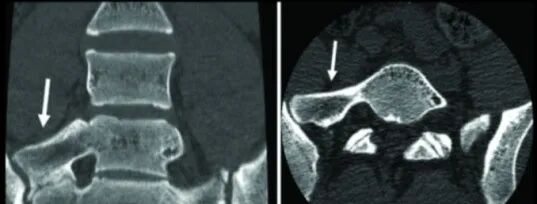

IIIa型:三维CT显示右侧横突与骶骨嵴融合

IIIb型:双侧横突与骶骨嵴融合

以目前国内的现状,首选薄层CT扫描并进行三维重建。